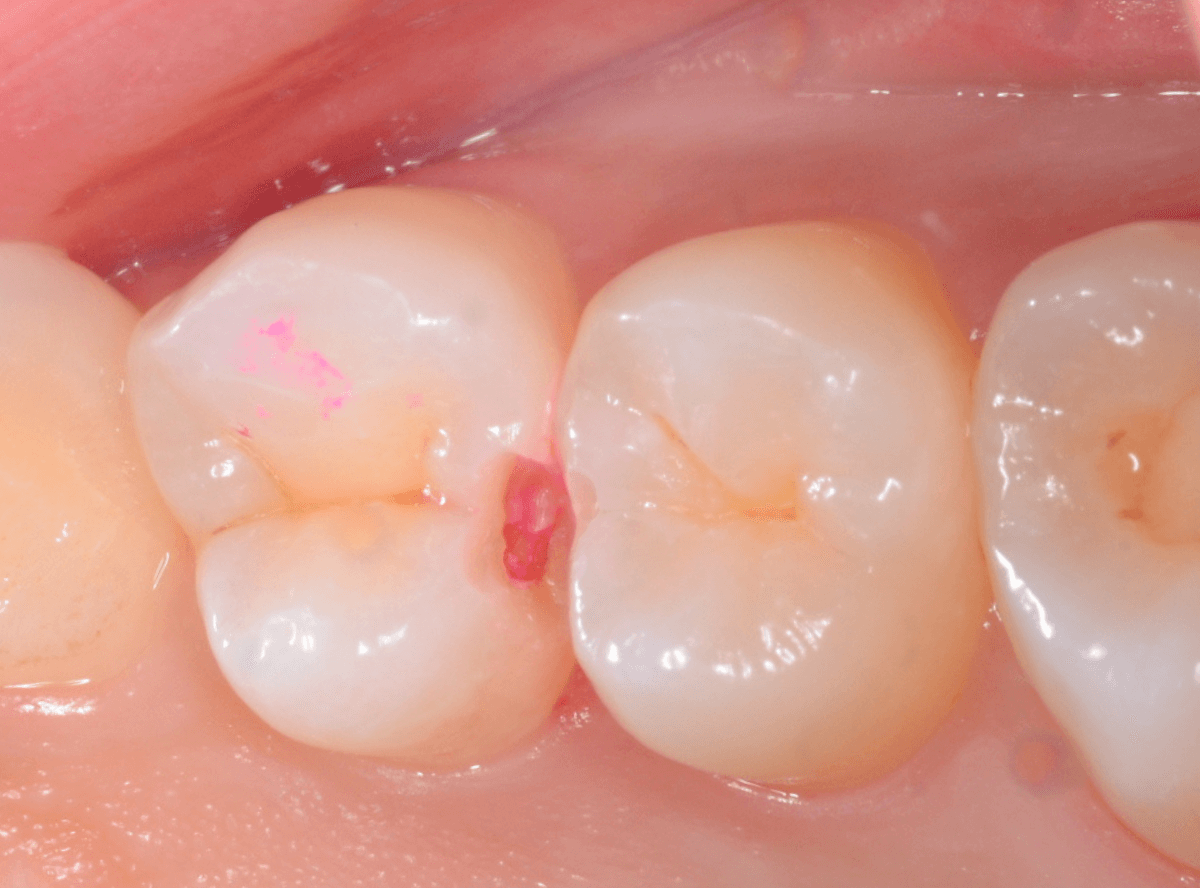

患者さんに説明後、慎重に歯を削って虫歯を探すと、やはり虫歯がありました(赤く染色されている部分です)。

虫歯の部分を全部除去したところです。

少し中で広がっていました。早めに治療ができてよかったです。

今回は、歯を削った部分にレジンをつめる簡単な処置ですみました。